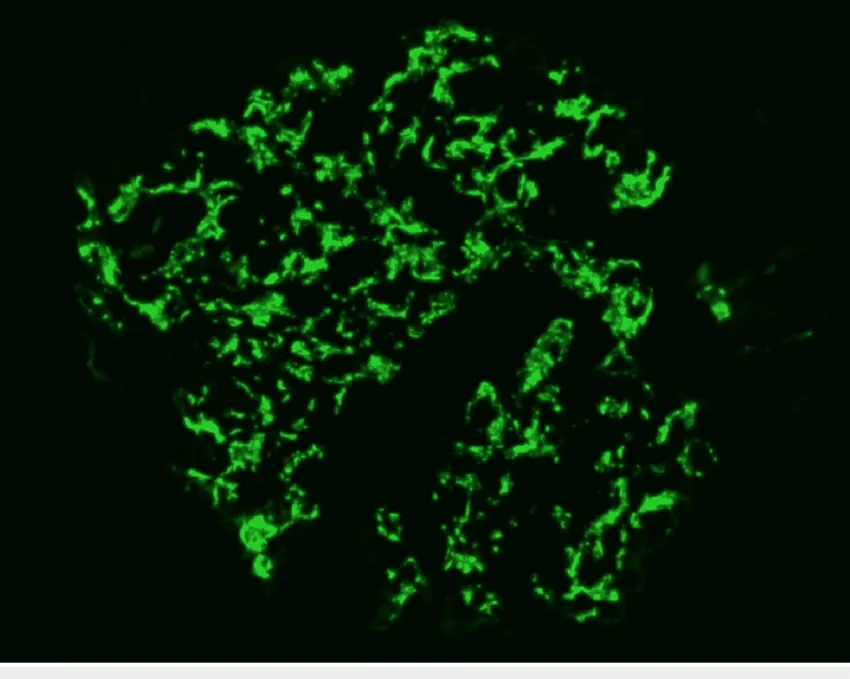

Diálise Peritoneal na Doença Renal Policística: existe algum motivo para não indicar?

Diálise Peritoneal na Doença Renal Policística: existe algum motivo para não indicar?

A DRPAD não é contraindicação à DP — e, na prática, muitos pacientes têm resultados comparáveis à hemodiálise. O “porém” está na mecânica: rins/hepatomegalia podem reduzir tolerância a volumes, aumentar risco de hérnias e extravasamentos, e piorar desconforto respiratório. Com técnica adequada (cateter presternal ou lateral, volumes menores, cicladora noturna e decúbito supino), a maioria das barreiras é contornável. Neste post, revisamos quando a DP é ótima, quando exigir cautela e como ajustar a prescrição para segurança e qualidade de vida.